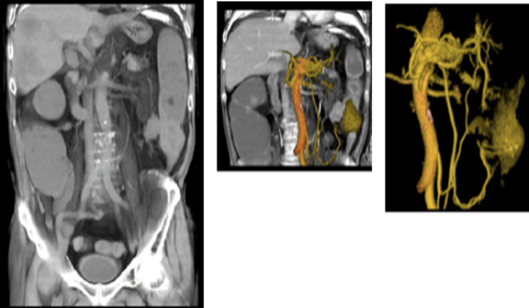

体幹部の検査においても、単純CTのアキシャル面から3D構築ができるため、幅広い視野で観察可能になり、転移の様な多臓器の観察にも有用であると考えています。

cv_uchida_06_big.png

非造影3D     造影後の3D

また、別の症例では、さすがにワンクリックではありませんが、非造影による単純スキャンデータから3D解析ツールを駆使して、このような尿路系の3D画像を構築することもできました。これも患者様に症例の解説を行う際にたいへん有用でした。